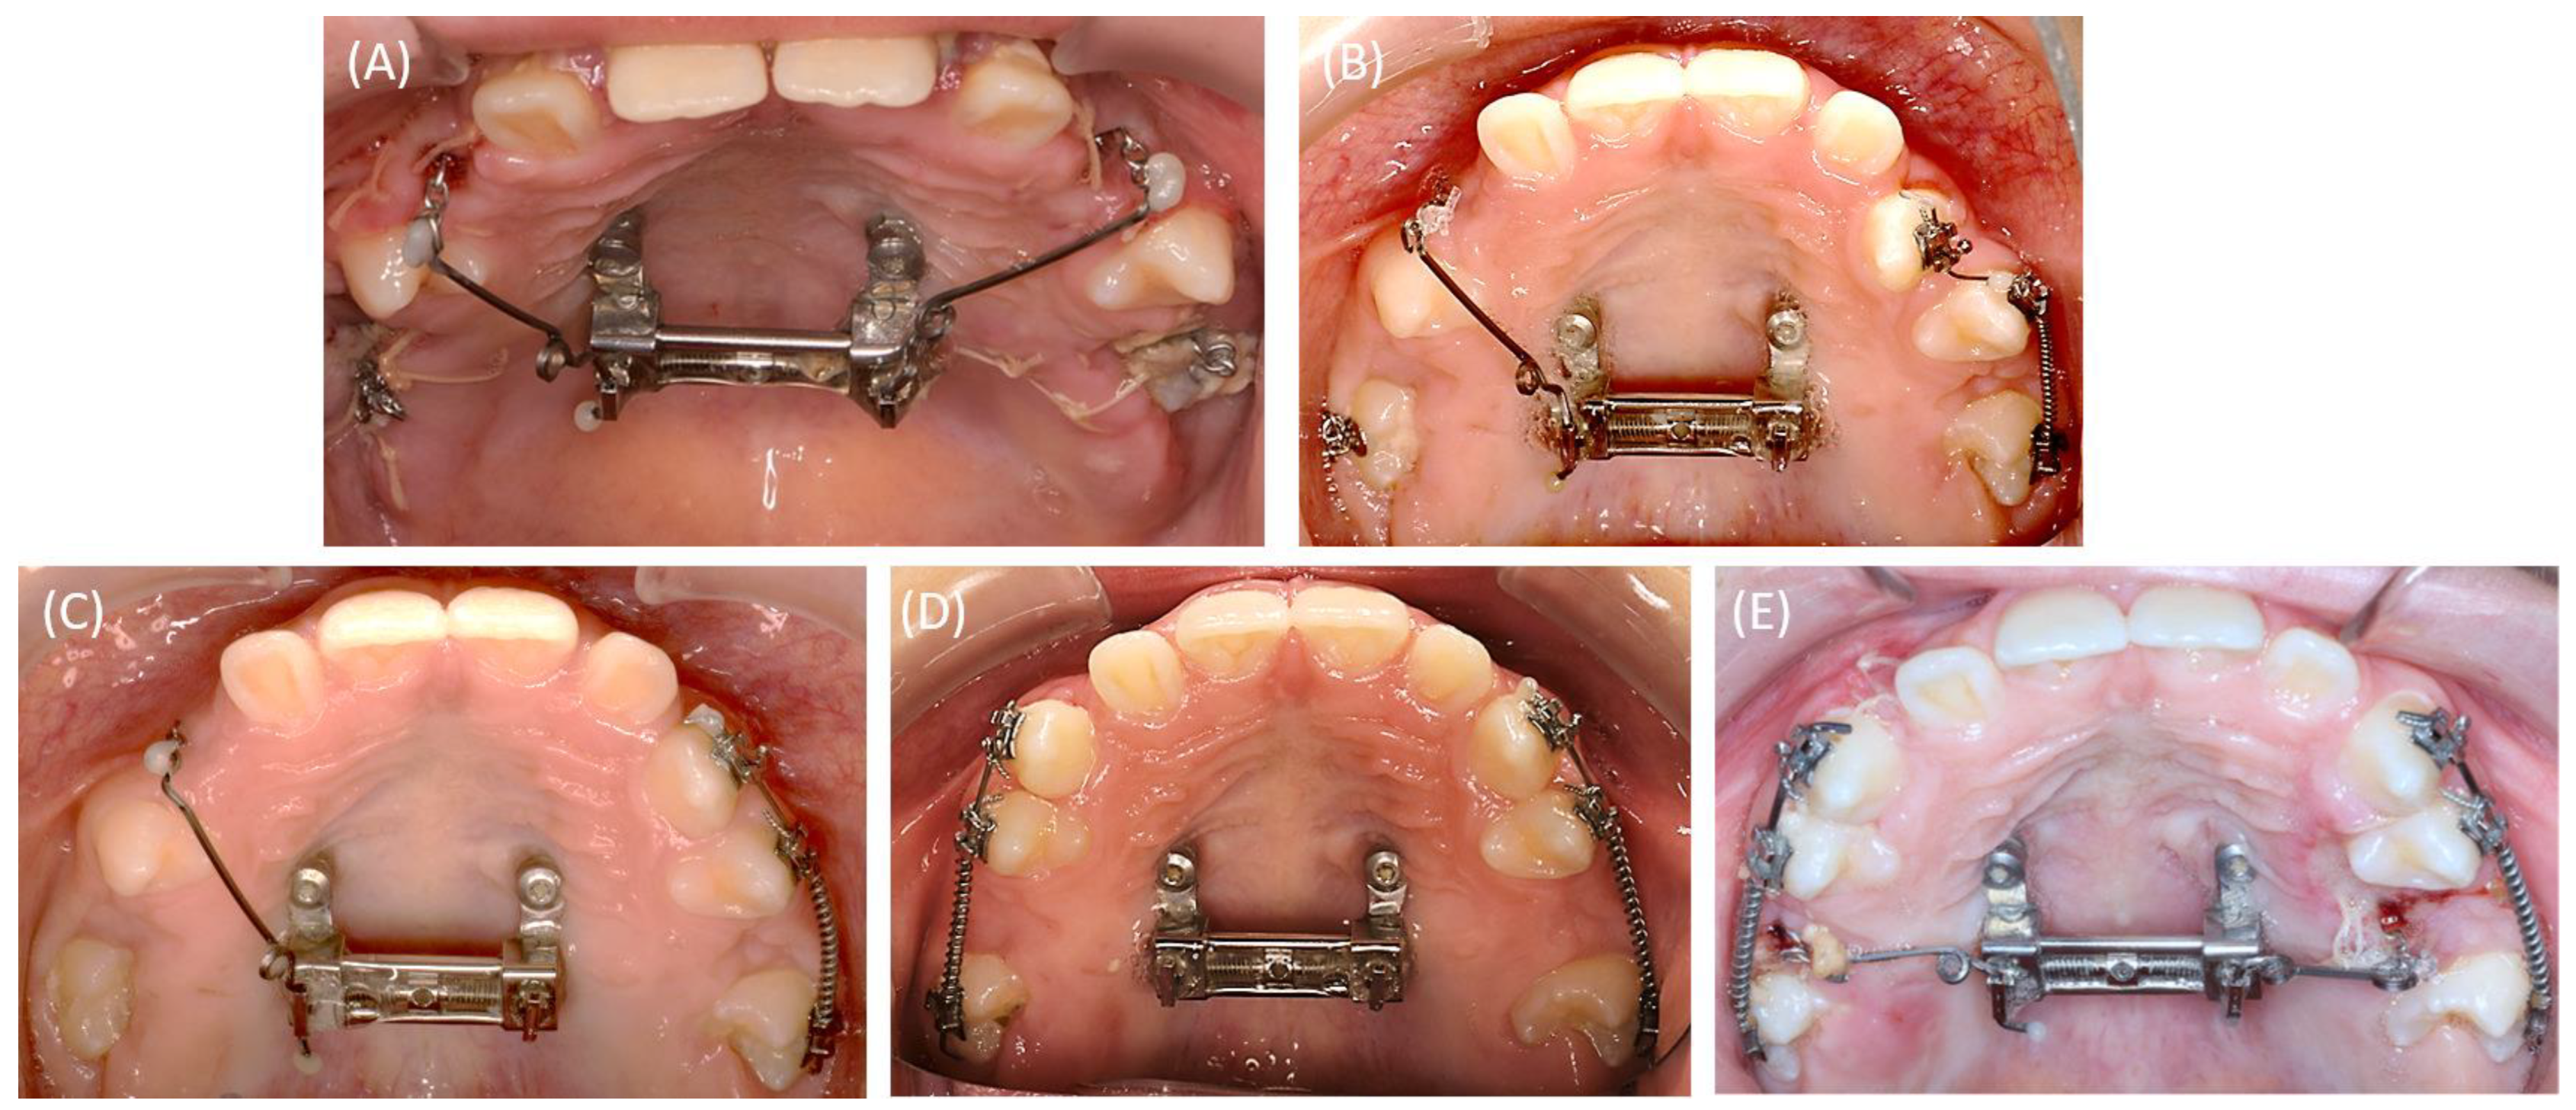

2.4.1. First Surgical Exposure of the Impacted Teeth and Insertion of the Mini-Implants

2.4.2. RPE Using the Skeletal-Anchorage Hyrax Appliance

2.4.3. Alignment of the Surgically Exposed Teeth by Using Skeletal Anchorage